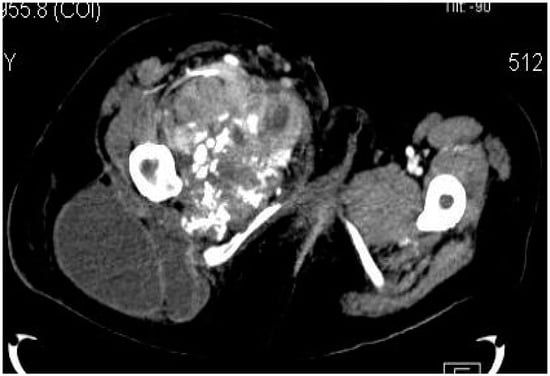

2.2. Imaging Examinations